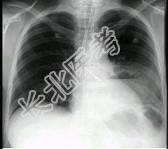

- 单项选择题女,36岁, 发热,胸痛咳脓痰十余天, 胸部正侧位如图,最可能的诊断为 ( )

A、左下肺周围型肺癌并空洞形成

B、左下肺脓肿

C、左下肺空洞型肺结核

D、左侧包裹性液气胸

E、急性胃扩张